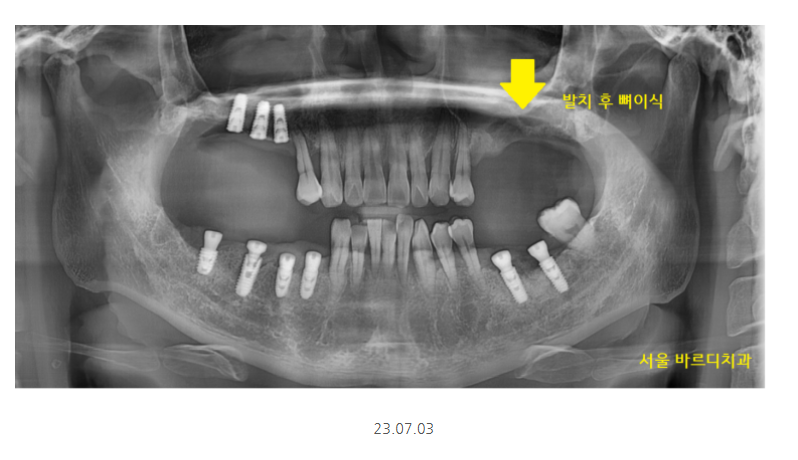

잇몸뼈가 많이 없는 상악의 경우

발치 후 뼈이식 하고 기다리다

임플란트를 심기도 하였습니다.

임플란트 뼈이식 흡연으로

충분히 기다렸습니다.

그동안 치아 상태는 이런 모습이셨어요.

어금니는 없고

식사는 하셔야하니까

7개월동안 임시틀니로 식사 하실 수 있게 했습니다.

얼마나 불편하셨겠어요.

매일 삼시세끼 밥을 먹는데

어금니 없는채로 7개월을 지내셨으니요..